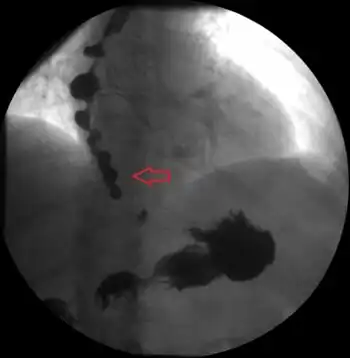

Esophageal spasm is a disorder of motility of the esophagus.[2]There are two types of esophageal spasm:[2]

- Diffuse or distal esophageal spasm (DES), where there is uncoordinated esophageal contractions

- Nutcracker esophagus (NE) also known as hypertensive peristalsis, where the contractions are coordinated but with an excessive amplitude.

Both conditions are linked to gastroesophageal reflux disease (GERD).[2] DES and nutcracker esophagus present similarly and can may require esophageal manometry for differentiation.[3] When the coordinated muscle contraction are irregular or uncoordinated, this condition may be called diffuse esophageal spasm. These spasms can prevent food from reaching the stomach where food gets stuck in the esophagus. At other times the coordinated muscle contraction is very powerful, which is called nutcracker esophagus. These contractions move food through the esophagus but can cause severe pain.[4]